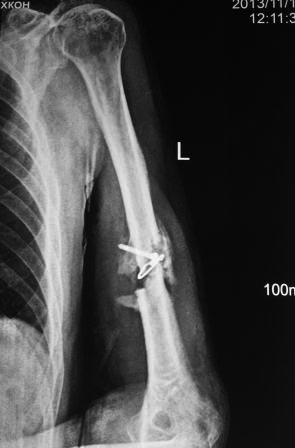

Пациент 1942г.р. 4 –месяца назад оперирован в экстренном порядке в другом областном неотложном центре, 20 дней назад гипс снят и направлен к нам. Пациент активный, оптимист, никогда ничем не болел. Локально: тугой ложный сустав с варусной деформацией, клиника полного повреждения лучевого нерва (со слов до операции также рука висела), контрактура локтевого сустава , разгибательная контрактура л/з сустава и пальцев, воспалительных изменений нет. От предложенного БИОС по финансовым соображениям отказался. Предварительный план лечения: удаление металлоконструкций, ревизия лучевого нерва (возможно, пластика нерва), освежение концов до появления "росы", и адаптация концов возможно по типу "русского замка", фиксация либо аппаратом Илизарова, либо пластиной (у нас обычные пластины ЦИТО типа DCP), возможно укорочение на 2-3 см, но это для плеча большого значения не имеет, главная ранняя и усиленная разработка движений в суставах руки. Уважаемые коллеги, не осуждайте строго за банальность, я пишу про то, что имеем и сможем , и если можно прошу помочь советом, или примерами из практики. С уважением Абдурашид.

Уважаемые коллеги, прошу прощения за задержку ответа. Операцию проводили 27.11.13г по настоятельной просьбе докторов там, где был оперирован, поэтому пришлось долго ждать контроль.Р-грамму и самого больного, только сегодня приехали. Операция более 4 часов, во время операции установлено полное повреждение лучевого нерва, концы булавовидно утолщены, дефект 2,5-см, с трудом и очень долго пришлось мобилизовать, частично был замурован костной мозолью . Кость укорочена на 3 см, пластика типа русского замка, в это время часть дистального отломка откололась, поэтому пришлось фиксировать винтом, и еще косо спицей., и/м 4-мя спицами, шов нерва, под нервом слой мышца, АВФ из двух колец с компрессией. Р-снимки прилагаются.